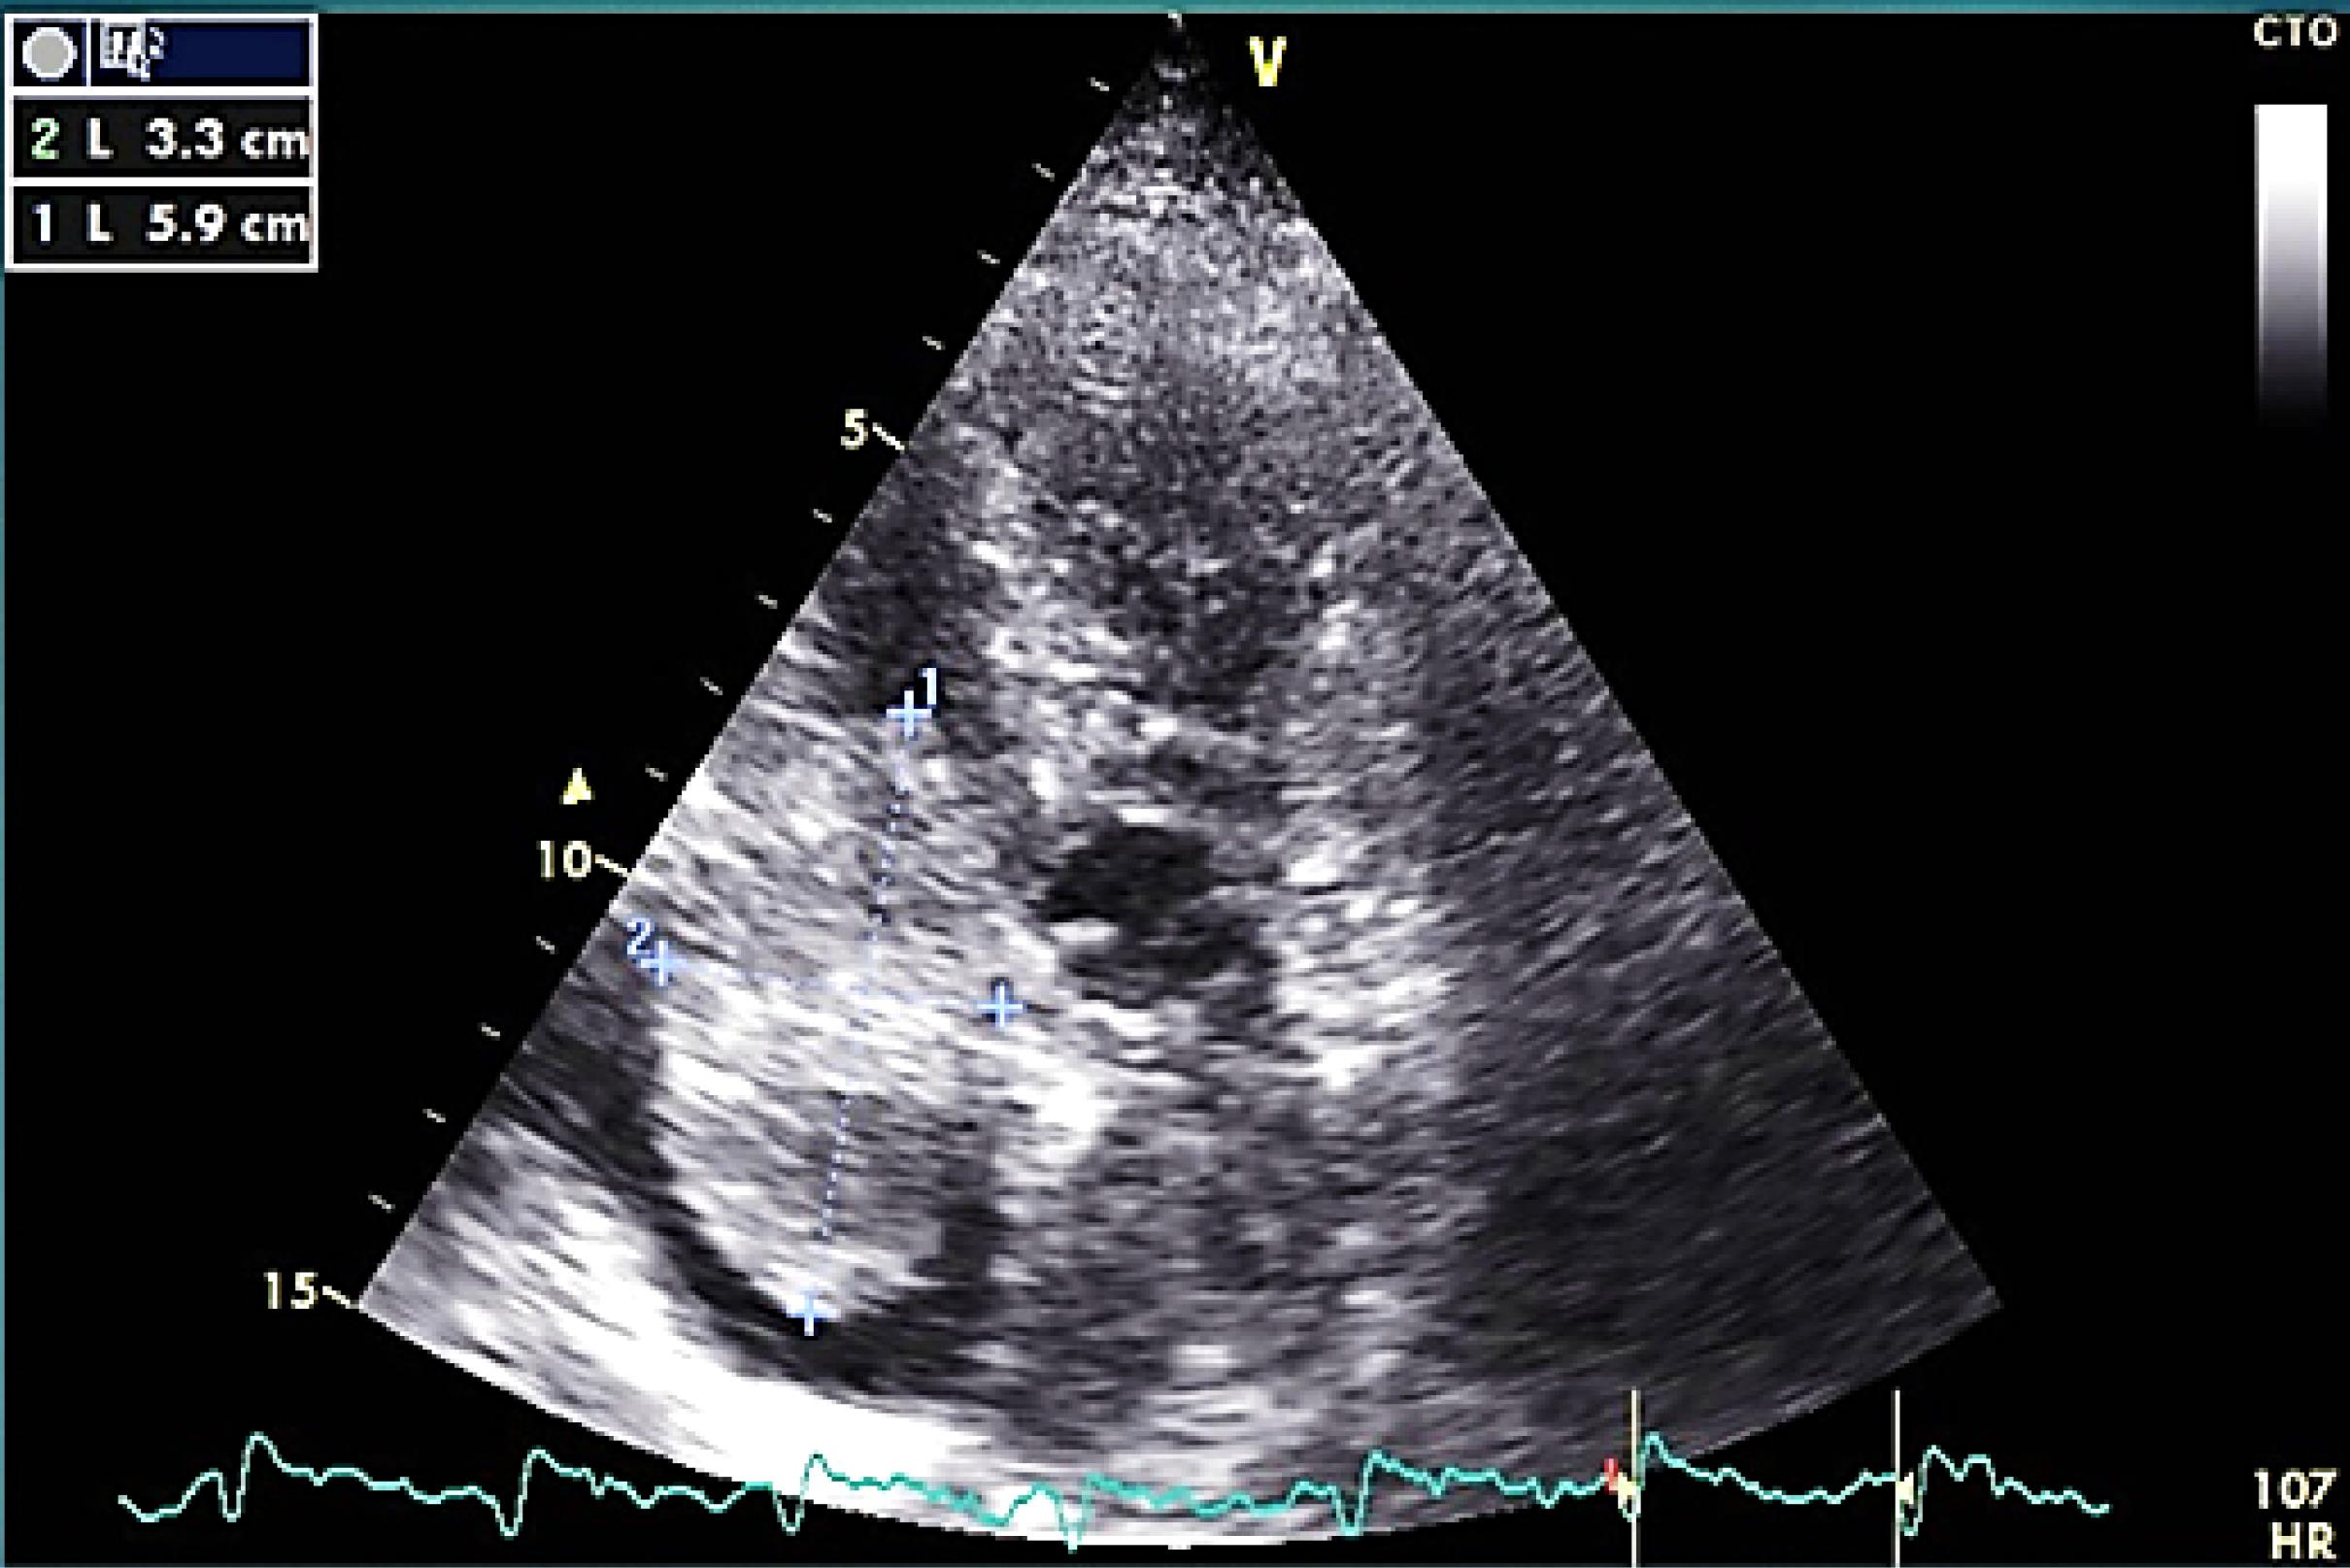

On transthoracic echocardiography a large size mobile pedunculated round-shape mass (5.9cm*3.3cm) in right atrium attached to inter-atrial septum at foramen oval level was detected (Figure 1).

Figure 1.

large size round shape mass in RA on TTE

The mass was none homogeneous and several filamentous apparatus was detectable on mass’s surface on echo. In cardiac cycle intermittent protrusion of mass into the TV and dynamic TV stenosis results in cyclic IVC dilation (Figure 2).